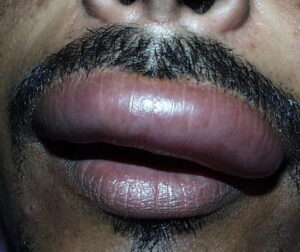

Angioedema is the swelling of deep dermis, subcutaneous or submucosal tissue due to vascular leakage.1 It was first described in 1586.2 Other terms, such as giant urticaria,3 Quincke edema,4 and angioneurotic edema,5 have also been used in the past to describe this condition. Clinically, angioedema is usually nonpitting and nonpruritic. The area of involvement is often skin-colored or slightly erythematous. Depending on the area of swelling, pain can be absent or mild, as in most peripheral or facial swelling, or can be very severe, as in gastrointestinal angioedema. Laryngeal swelling is life-threatening. It should be treated as a medical emergency.

Patients usually describe swelling of the face (eg, eyelids, lips), tongue, hands, and feet. It can be acute or chronic, and each episode of angioedema may last a few hours to a few days. A local burning sensation and pain can be observed without pronounced itchiness or local erythema. Abdominal pain can sometimes be the only presenting symptom of angioedema. Throat tightness, voice changes, and trouble breathing may indicate airway involvement.

For skin involvement, examination can easily identify areas of swelling with or without erythematous skin, often with ill-defined margins. Some cases of angioedema occur in patients with urticaria.

Uvula or tongue swelling can be visualized directly (see image below). However, a laryngoscopy is needed to assess laryngeal or vocal cord involvement.